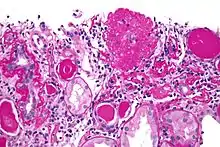

| Light micrograph of focal segmental glomerulosclerosis, hilar variant. Kidney biopsy. PAS stain. | |

The individual components of the name refer to the appearance of the kidney tissue on biopsy: focal—only some of the glomeruli are involved (as opposed to diffuse), segmental—only part of each glomerulus is involved (as opposed to global),[19] glomerulosclerosis—refers to scarring of the glomerulus (a part of the nephron (the functional unit of the kidney)). The glomerulosclerosis is usually indicated by heavy PAS staining and findings of immunoglobulin M (IgM) and C3-convertase (C3) in the sclerotic segment.[20]